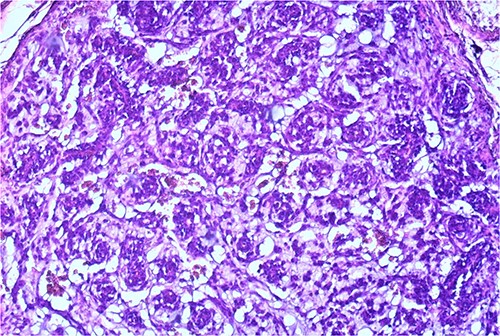

The macroscopic pathology report revealed the total dimension of the removed tissue to be 10.5 × 8.5 × 10.5 cm. However, the tumor itself had dimensions of 8 × 7.5 × 7 cm, surrounded by a pseudo capsule. The tumor was described to be multicystic, formed by loculi filled with hemorrhagic and partially with yellowish gelatinous myxoid content. In its periphery, yellowish tumor tissue was present (Fig. 3). Microscopic findings described a tumor made of myxoid stromal nodules and small capillaries concentrically surrounded by monomorphic round cells with mild nuclear pleomorphism. Large pseudo-angiomatous spaces filled with blood were seen in some of the nodules. Part of the nodules was hypocellular, made mostly by myxoid stroma and stellate cells. A thick fibrous pseudo capsule with numerous multifocal deposits of hemosiderin deposits was present peripherally. Tumor tissue infiltrates the abdominal wall muscles (Figs 4 and 5).

Small capillaries lined by relatively monomorphous round cells, with mild pleomorphism and sparse mitotic activity, surrounded by myxoid stroma (HeEo, ×100).

On immunohistochemical staining, tumor cells were positive on Vimentin, Smooth Muscle Actin (SMA), and focally on CD34. They stained negative on Desmin, Caldesmon, CD31, HMB 45, GFAP, CKAE1/AE3, CK7, EMA, S100, CD99, and p63. The tumor’s proliferation index after staining with Ki-67 was ~5% (Fig. 6a–c).